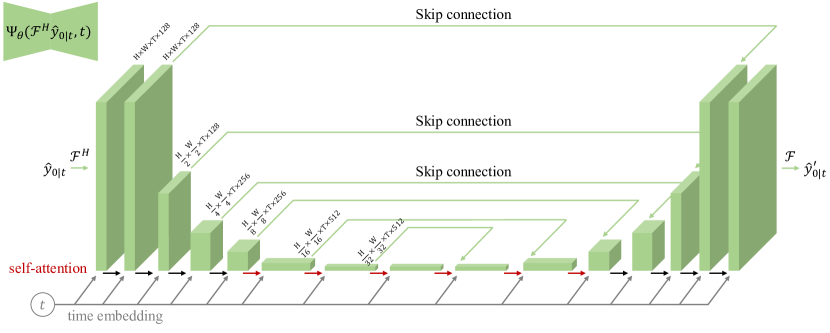

where represents a Fourier transform applied to the estimated clean k-space data to convert it into - space, and denotes the inverse Fourier transform operation. The represents a 3D CNN that captures the temporal dynamics. , where, in this study, we employ a 3D U-Net (Supporting Information Figure 7) for .

Figure S7. 3D U-Net architecture used for the - network . The input has dimensions (H, W, T, 2C), where H and W represent the spatial height and width, T denotes the number of time frames, and C corresponds to the number of coils, with real and imaginary components stacked. The network employs 3D convolution kernels of size 333 and is structured as an encoder-decoder architecture with bottleneck blocks. Each encoder stage comprises two residual blocks, with convolutional downsampling applied exclusively to the spatial dimensions (H and W), except at the final level. The decoder stages contain three residual blocks and use 2 nearest-neighbor upsampling followed by convolutions to process inputs from the previous level. Skip connections between encoder and decoder stages ensure efficient feature propagation and preserve both spatial and temporal details. The model integrates “Self-Attention” modules, indicated by red arrows, to enhance global contextual understanding. Additionally, each residual block receives inputs from the preceding layer and time-step embeddings, encoding information about the current diffusion time step. This design enables the network to effectively capture and process dynamic - features, ensuring high spatial and temporal fidelity in the reconstructed outputs.